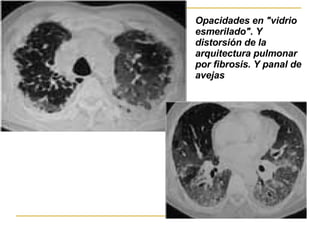

Patrón intersticial   Se caracteriza por la existencia de líneas o rayas en el parenquima pulmonar   Patrón lineal o linfangítico, que corresponden al engrosamiento de los septos interlobulillares infiltrado  intersticial  inflamatorio y depósito anómalo de fibras del tejido conectivo que pueden conducir a una fibrosis pulmonar que a su vez puede evolucionar hacia un patrón en pana l

Opacidades intersticiales de patrón reticular grueso, de predominio periférico, con áreas que sugieren patrón de "panal de abejas". Neumonía  intersticial  descamativa :  zonas de pulmón sano de inflamación,  macrófagos   de fibrosis intersticial  fibroblastos proliferantes  cambios de pulmón en panal.  heterogeneidad

Opacidades en "vidrio esmerilado". Y   distorsión de la arquitectura pulmonar por fibrosis.  Y panal de avejas